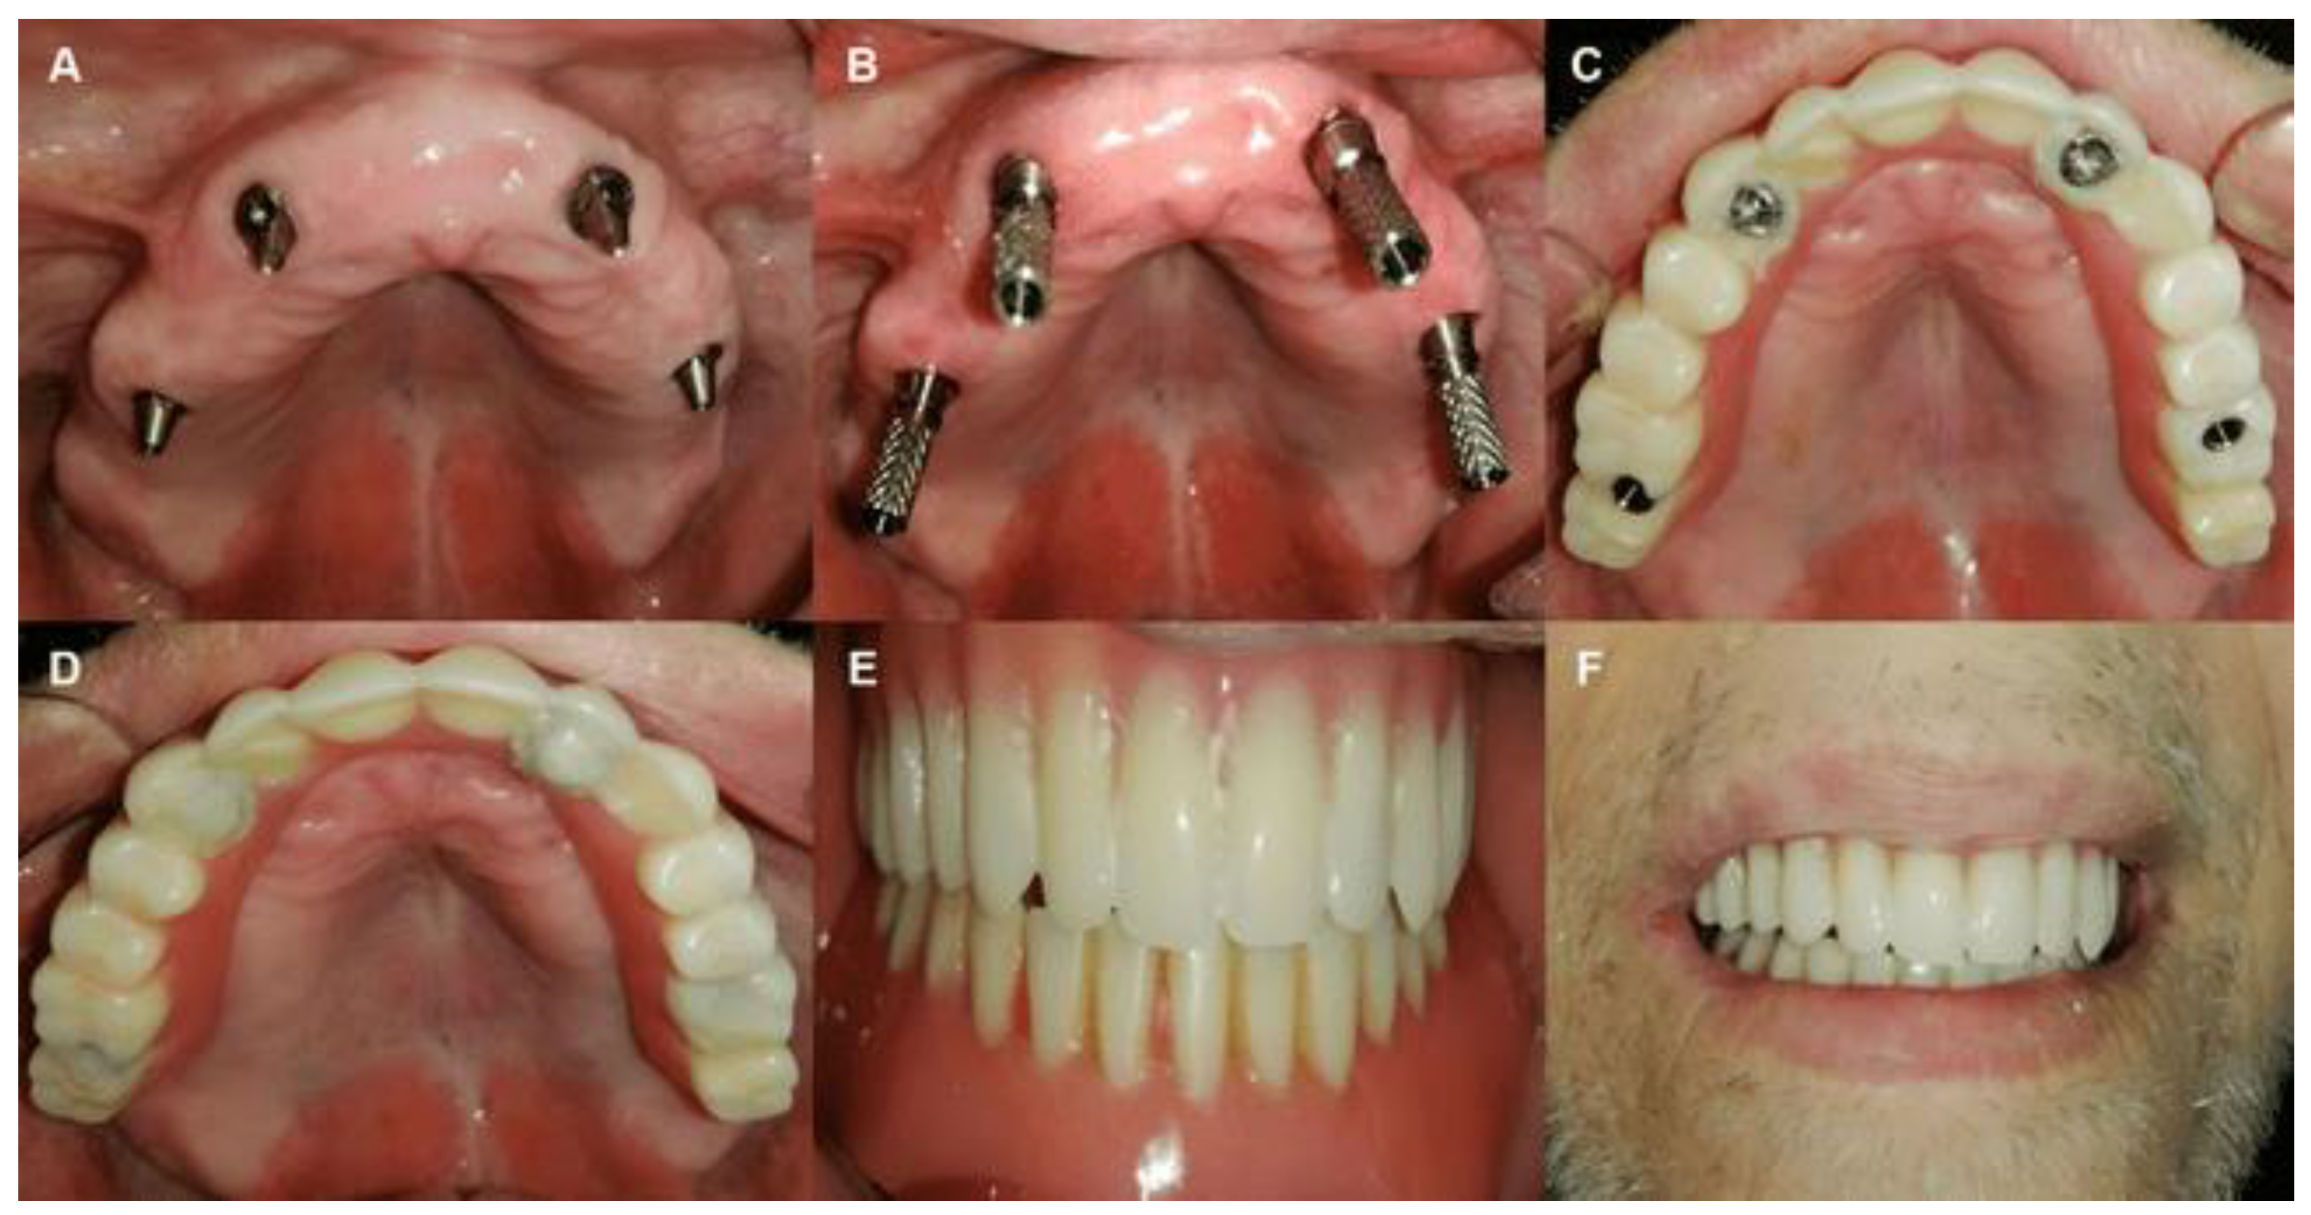

After a healing period of 4 months, post-operatively a final prosthetic rehabilitation could be started as follows (Figure 7 and Figure 8): Unscrew the provisional denture; Attach open tray multi-unit impression-transfer to multi-unit abutments; Lute the impression transfers together with metal wire to ensure accuracy; Make sure the tray clears the open tray impression transfers; Take the open tray impression by using light and heavy body impression materials; The final titanium prosthetic framework was made and included 12 teeth with a maximum of the one-unit cantilever from aesthetic resin material; The final prosthesis should seat firmly against the soft tissue, and be retained by screws with a moment of 15 N.cm; Block out screw hollows with acrylic or flow composite.

Figure 7. Steps of final prosthesis: A. resin bar, B. Metal bar, C and D. Final prosthesis, E and F. Final prosthesis after adjusting the occlusion.

Clinical evaluation of the implant survival was calculated at each re-assessment (4- and 12-months follow-up period post-operatively) (Figure 10), plaque index (PI) was evaluated on the mesial, distal, buccal, and palatal surface of the multi-unit abutments at each re-assessment (4 and 12 months).

Figure 10. A. pre-operative smiling, B. smiling after provisional prosthesis fixation, C. smiling after final prosthesis fixation.